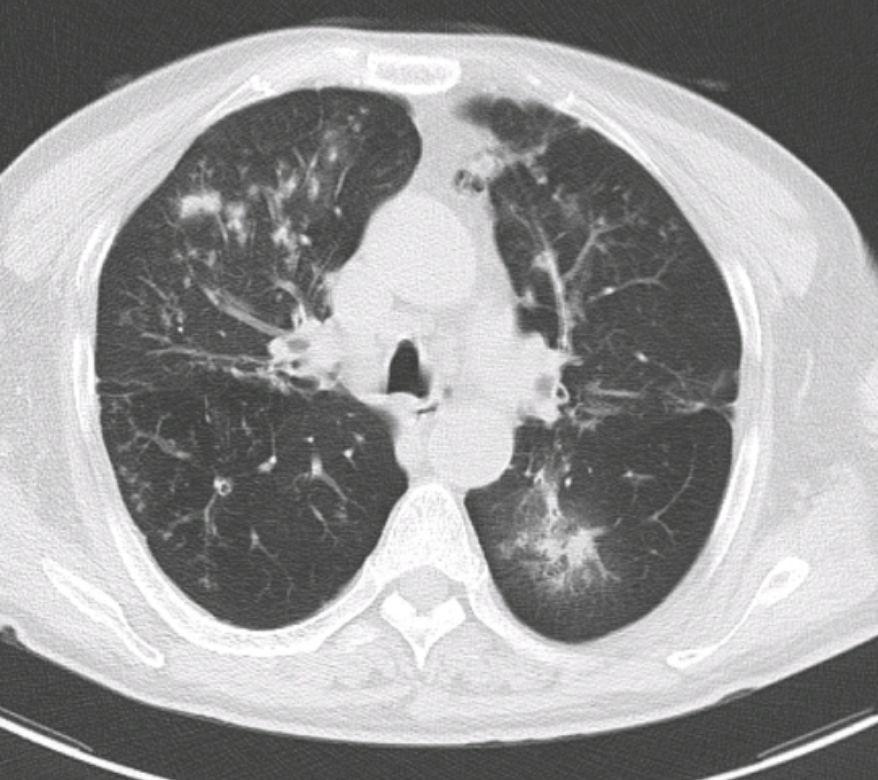

两个信号,说明你的肺结节,不能再拖了! 第一:结节相关症状突然出现或加重 如果之前没有任何不适,近期突然出现不明原因的干咳、咳嗽带痰,甚至痰液中带血丝、铁锈色痰;或是频繁感到胸闷气短、胸痛位置固定且持续不缓解,这些都可能是结节刺激肺部组织、引发局部炎症或病变进展的表现。 第二:影像学检查提示结节 “高危特征” 如果复查时发现肺结节的大小、形态、密度发生明显变化,变成不规则形状,出现 “分叶、毛刺、胸膜牵拉” 等,密度从磨玻璃样变为实性或混合磨玻璃实性,这些都是临床上判断结节恶性风险较高的关键指标,要及时干预。